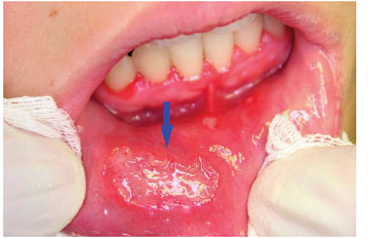

疱疹样复发性阿弗他溃疡"满天星"